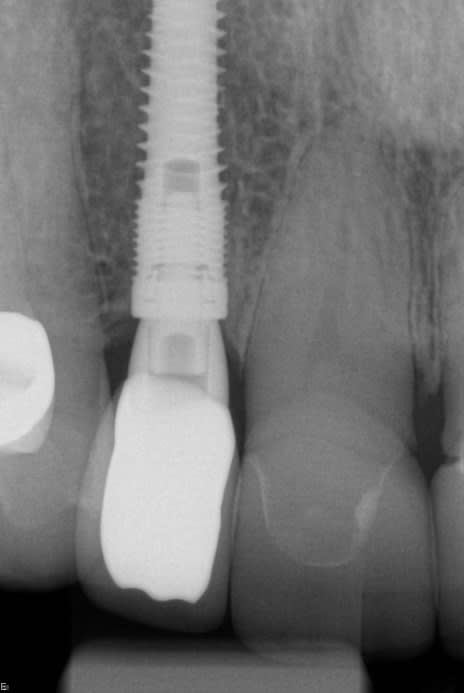

With the patient under local anesthesia and intravenous (IV) sedation, tooth No. 4 was extracted atraumatically, osteotomy was performed for immediate placement of a 4.5-mm x 11.5-mm implant (Genesis) (Figure 4 and Figure 5), followed by bone grafting using a corticocancellous mineralized freeze-dried bone allograft to manage the implant–alveolus discrepancy, and a healing cap was placed. At Visit 3, normal healing and good tissue tone were observed (Figure 6).

In July 2012 the stock abutment (using the standard platform-switched connection) and final porcelain-fused-to-metal (PFM) crown were placed; gingival health was excellent and showed a midfacial PD of 1 mm (Figure 7). At 18 months (Visit 7) a midfacial probing depth of 3 mm without bleeding was noted (Figure 8). Endodontic treatment was performed on tooth No. 5 after completion of the implant restoration (Figure 9). A subsequent follow-up photograph from January 2015 (Figure 10) shows the facial view of the final crown in occlusion.

In February 2012 the patient enrolled in the multicenter study. Using a flapless access approach with the patient under nitrous-oxide sedation, one of the periodontist authors (ETS) removed keratinized tissue from the proposed implant site using a 4-mm biopsy punch. Osteotomy was prepared using a surgical guide for the placement of a 4.5-mm x 10-mm tapered implant (Genesis), which was anchored in the floor of the maxillary sinus (using osteotomes) for optimal primary stability, at an insertion torque of 45 Ncm (Figure 32).

One month later, the custom UCLA abutment (Figure 33) was attached to the fixture using a platform-switched connection, with an insertion torque of 35 Ncm. The final PFM crown was cemented using methylmethacrylate (C&B-Metabond® Quick! Cement System, Parkell, www.parkell.com). The occlusion and the patient’s nightguard were checked and adjusted to the new restoration.

The midfacial PD at Visit 7 (18-month follow-up) was 2.5 mm, with no bleeding and good gingival tone (Figure 34). Good radiographic osseointegration (Figure 35) and excellent soft-tissue and restoration esthetics were observed at this visit (Figure 36 through Figure 38). The patient was last seen in February 2015 (almost 3 years after implant placement), at which time favorable hard- and soft-tissue levels and optimal esthetics were confirmed clinically and radiographically (Figure 39 and Figure 40).

In February 2012 the patient enrolled in the multicenter study, and a 5.5-mm x 11.5-mm implant (Genesis) was placed (Figure 42). Minor contour bone grafting of the site was also performed using autogenous bone directly against the buccal cortex and layered thereafter with a corticocancellous allograft (Puros) along the lateral aspect of the implant. This was done to increase the peri-implant bone and mucosal thickness (existing bone thickness was <1 mm on the buccal aspect) in an effort to improve parameters that would reduce the incidence of recession over the long term.

The 5.5-mm implant platform was used to accommodate the high occlusal load typically associated with the molar area and to optimize the esthetic emergence profile of the final restoration, neither of which would have been feasible with a narrower implant, even in the presence of more robust socket augmentation. A healing abutment was placed (Figure 43).

A high implant stability quotient (Osstell® ISQ = 80) (Osstell, www.osstell.com) and insertion torque values >50 Ncm allowed the prosthetic phase to begin in April 2012 (Visit 3). Figure 44 shows the periapical radiograph at Visit 3; Figure 45 shows good healing and tissue tone at this visit as well.

The final open-tray polyvinylsiloxane impression (Aquasil®, DENTSPLY International, Inc, www.dentsply.com) was also obtained at Visit 3. The impression coping was radiographically verified for accurate seating. The fixture analog was placed into the laboratory model, and a stock abutment (Genesis) was used by the laboratory to create a PFM crown with a screw-access hole in its occlusal surface (Figure 46).

In the prosthetic phase, the restorative dentist chose to use an indirect cementation technique to minimize the risk of cement entrapment/sepsis if the crown were to be cemented intraorally. In August 2012 the abutment and crown were tried in and, once proper seating and fit had been verified radiographically (Figure 47), the abutment was removed and the crown cemented extraorally with resin-modified glass-ionomer cement (FujiCem™, GC America, www.gcamerica.com). After removal of excess cement, the abutment–crown unit was then seated intraorally and torqued into the implant fixture to 35 Ncm using the standard platform-switched connection for this stock abutment. The access hole was sealed with Teflon tape and, after etching with 9.5% hydrofluoric acid, filled with nanohybrid composite resin (Renamel® NANO™, Cosmedent, www.cosmedent.com). The crown was then contoured, adjusted, and polished.

Figure 47 shows the stock abutment connected to the implant prior to extraoral cementation to the final PFM crown, which was followed by screw-retained placement (Visit 4). Figure 48 shows a good emergence profile, good gingival health, and a PD of 1 mm approximately 3 weeks after cementation (6-month follow-up), and Figure 49 confirms excellent esthetics and good occlusion at the 18-month follow-up visit (Visit 7).

Figure 50 shows the final periapical view of the osseointegrated implant, abutment, and final screw-retained PFM crown at the 18-month follow-up (Visit 7). Bone loss of 1 mm to 2 mm is radiographically apparent around the implant in this view, as compared to 2 months post-implant placement (Figure 44). However, this is likely of little or no clinical significance, because no PD recorded at 18 months exceeded 3 mm (Table 6). The process by which this bone loss probably occurred is discussed below.